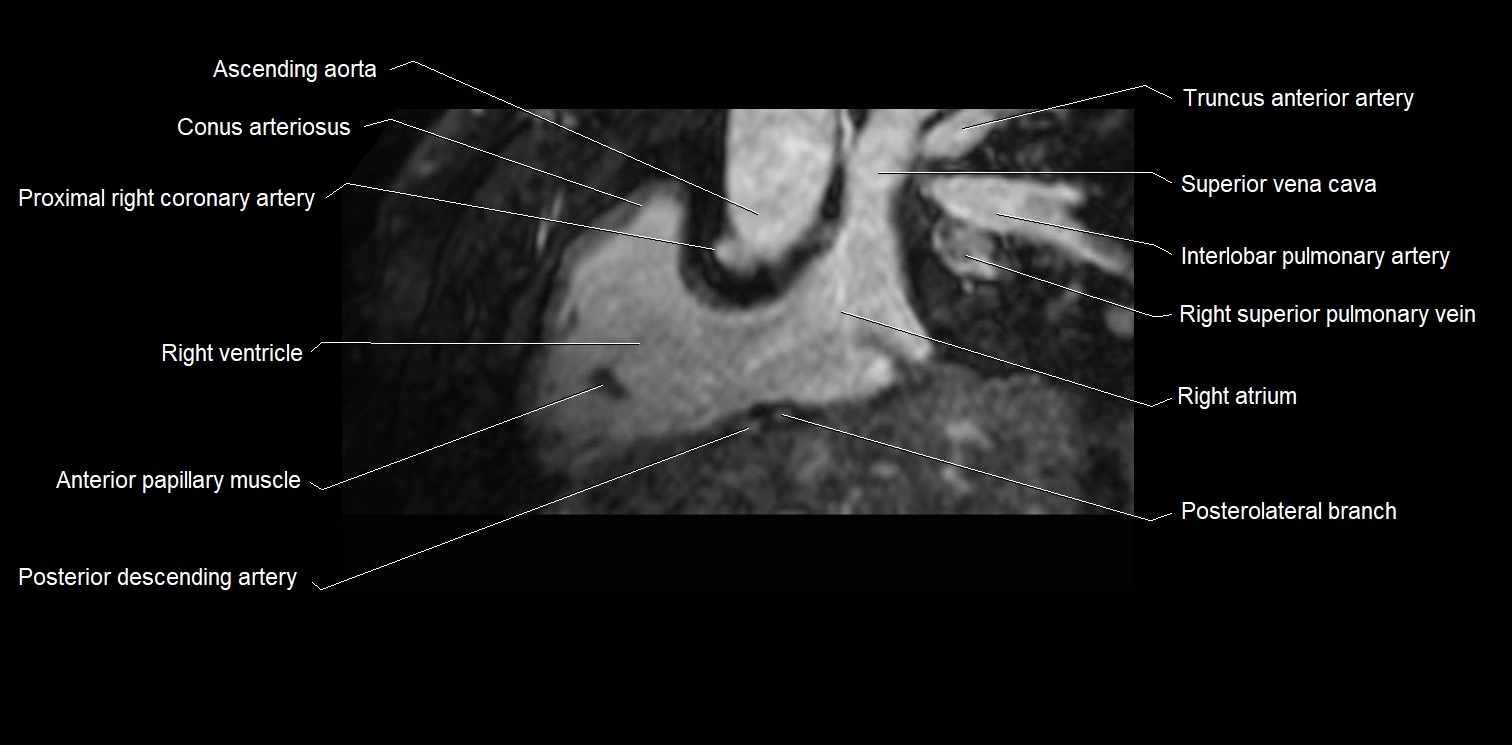

- Ascending aorta

- Conus arteriosus

- Anterior papillary muscle

- Right ventricle

- Right atrium

- Right superior pulmonary vein

- Right posterior descending coronary artery (Right PDA)